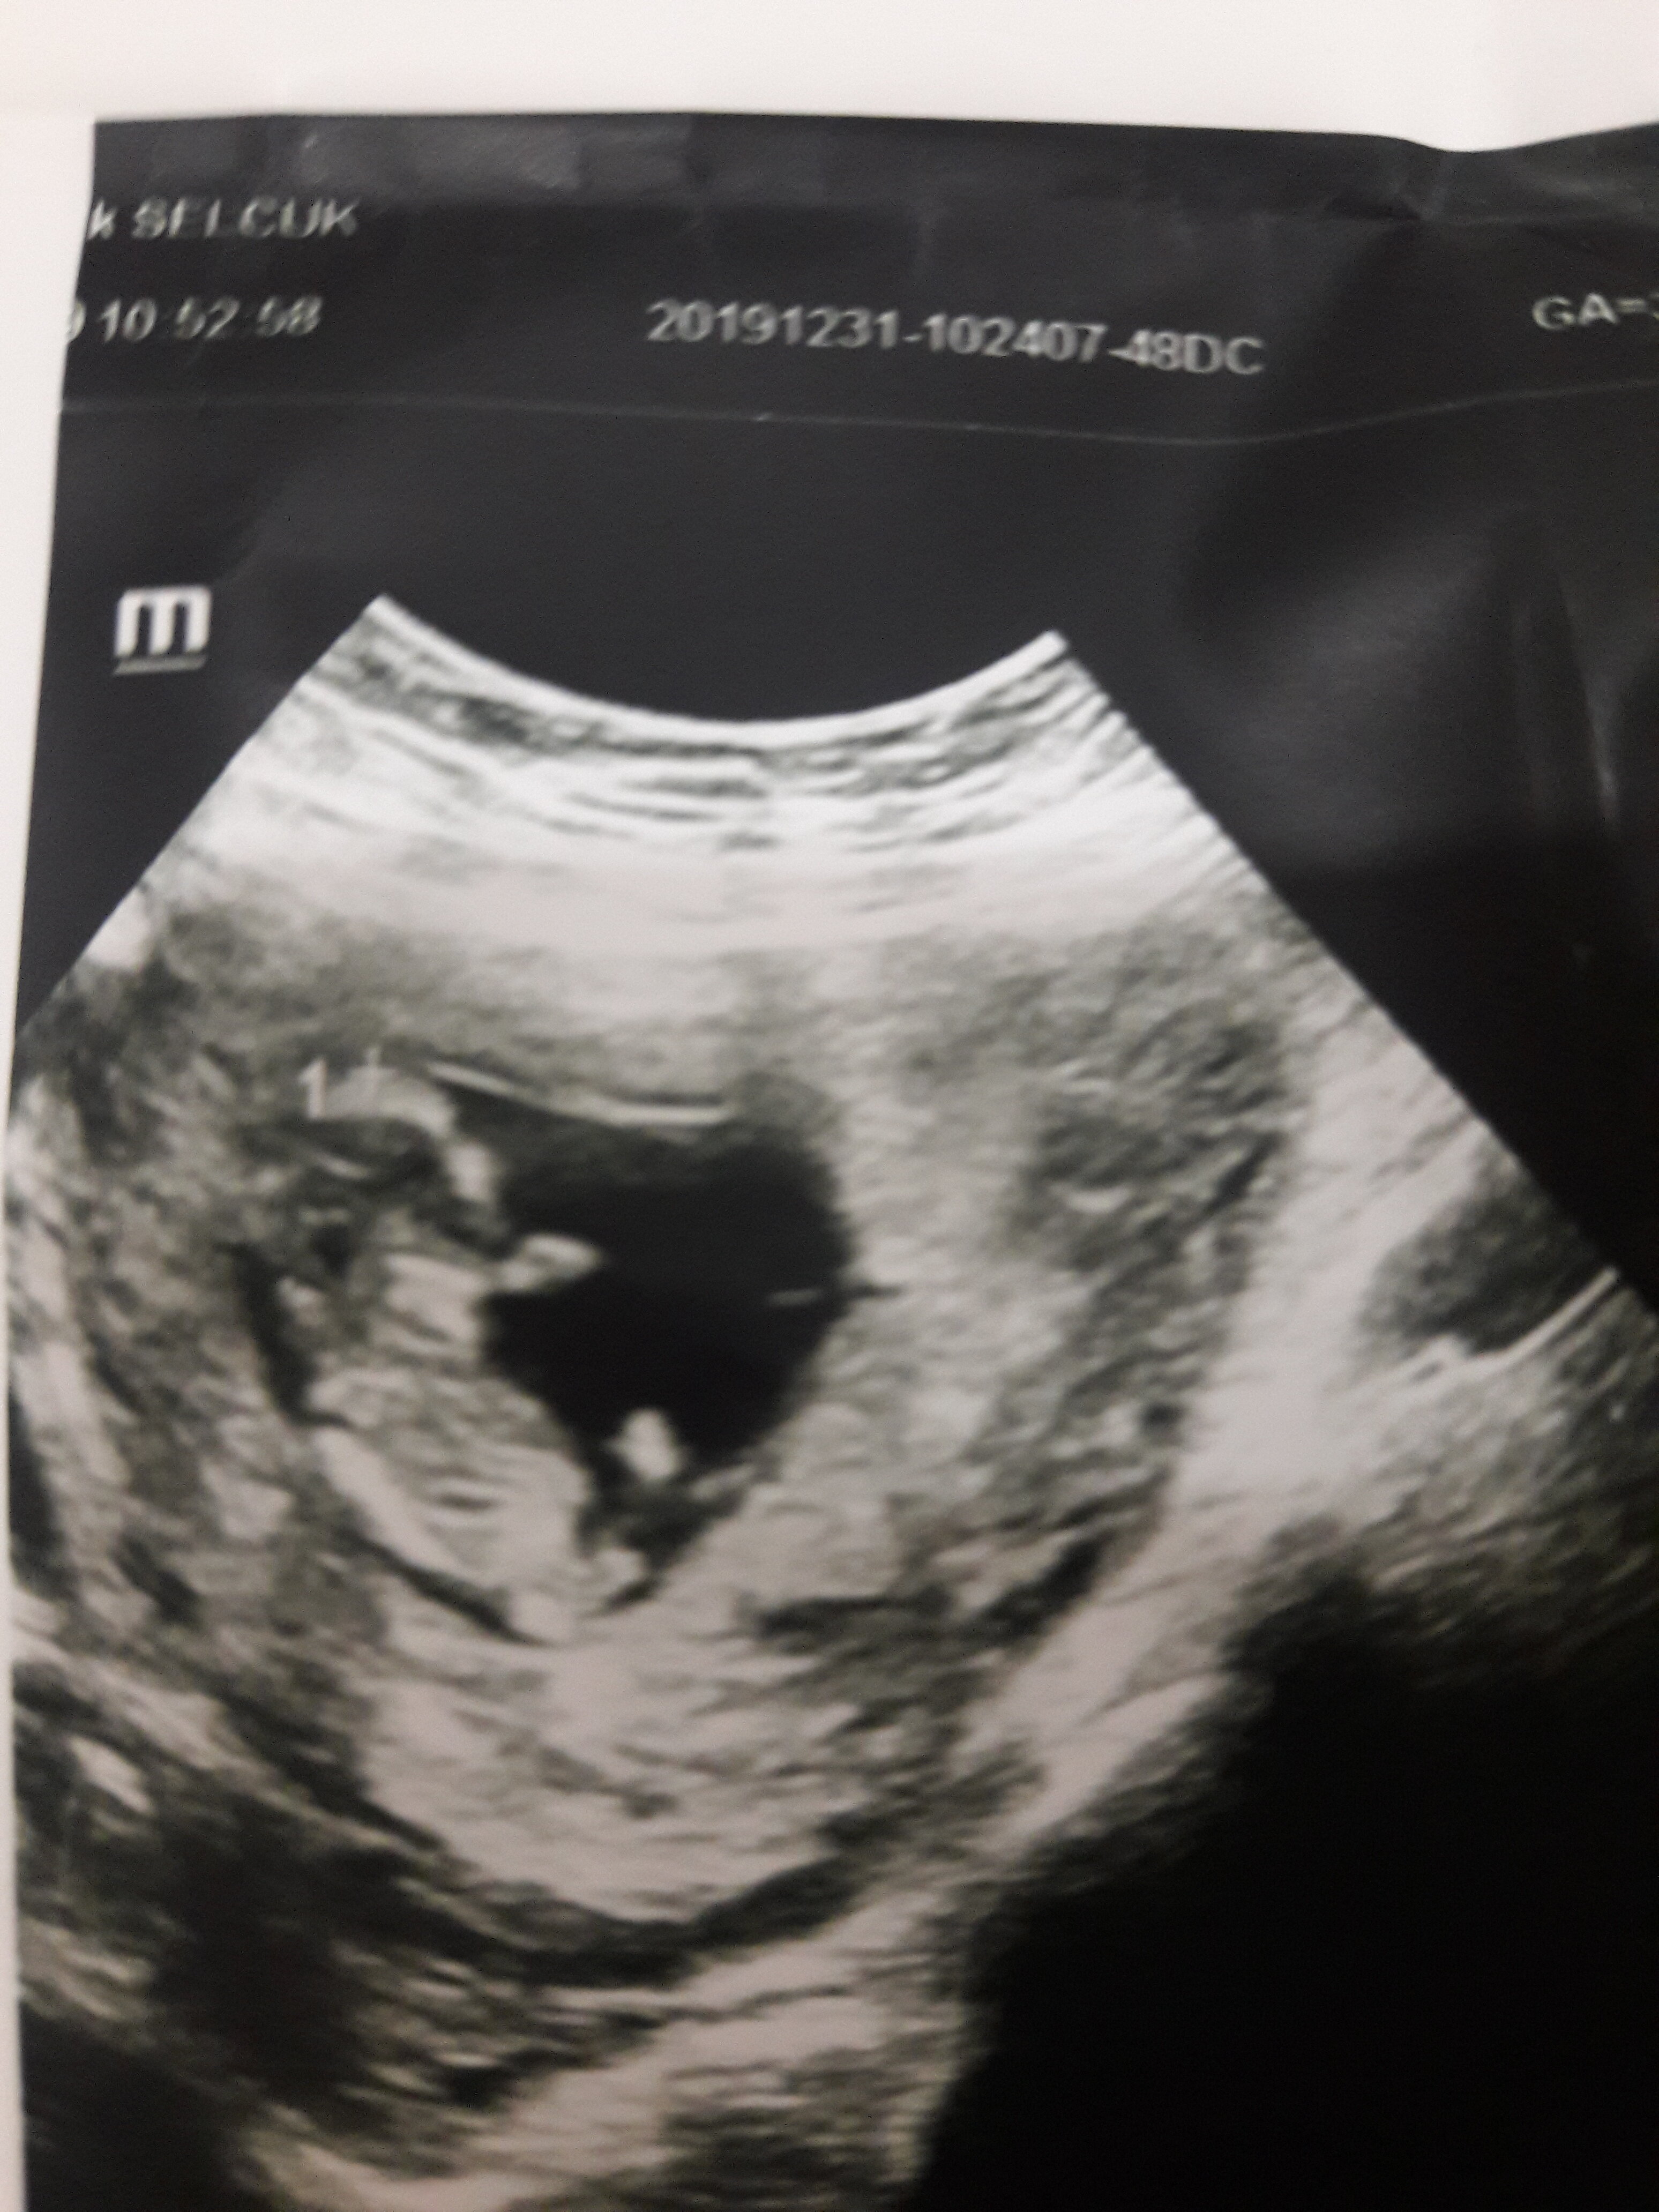

Sümbül 63 Yeni Üye Üye 1 Ocak 2020 #18 Merhabalar benimde usg goruntume yorum yapabilirmisiniz kizmi erkekmi sizce Ekli dosyalar 20191231_104945.jpg 1,5 MB · Görüntüleme: 480

SadmiN ♥ Evli Mutlu Çocuklu ♥ Yönetici 1 Ocak 2020 #19 Sevgili @Sümbül 63 malesef net değil dolayısı ile yorum yapamıyorum yakın lazım ve tabiki en önemlisi net lazım.

Sevgili @Sümbül 63 malesef net değil dolayısı ile yorum yapamıyorum yakın lazım ve tabiki en önemlisi net lazım.

Sümbül 63 Yeni Üye Üye 2 Ocak 2020 #20 Bu sekilde netmi acaba Ekli dosyalar 15779142171731587885330.jpg 1,3 MB · Görüntüleme: 433